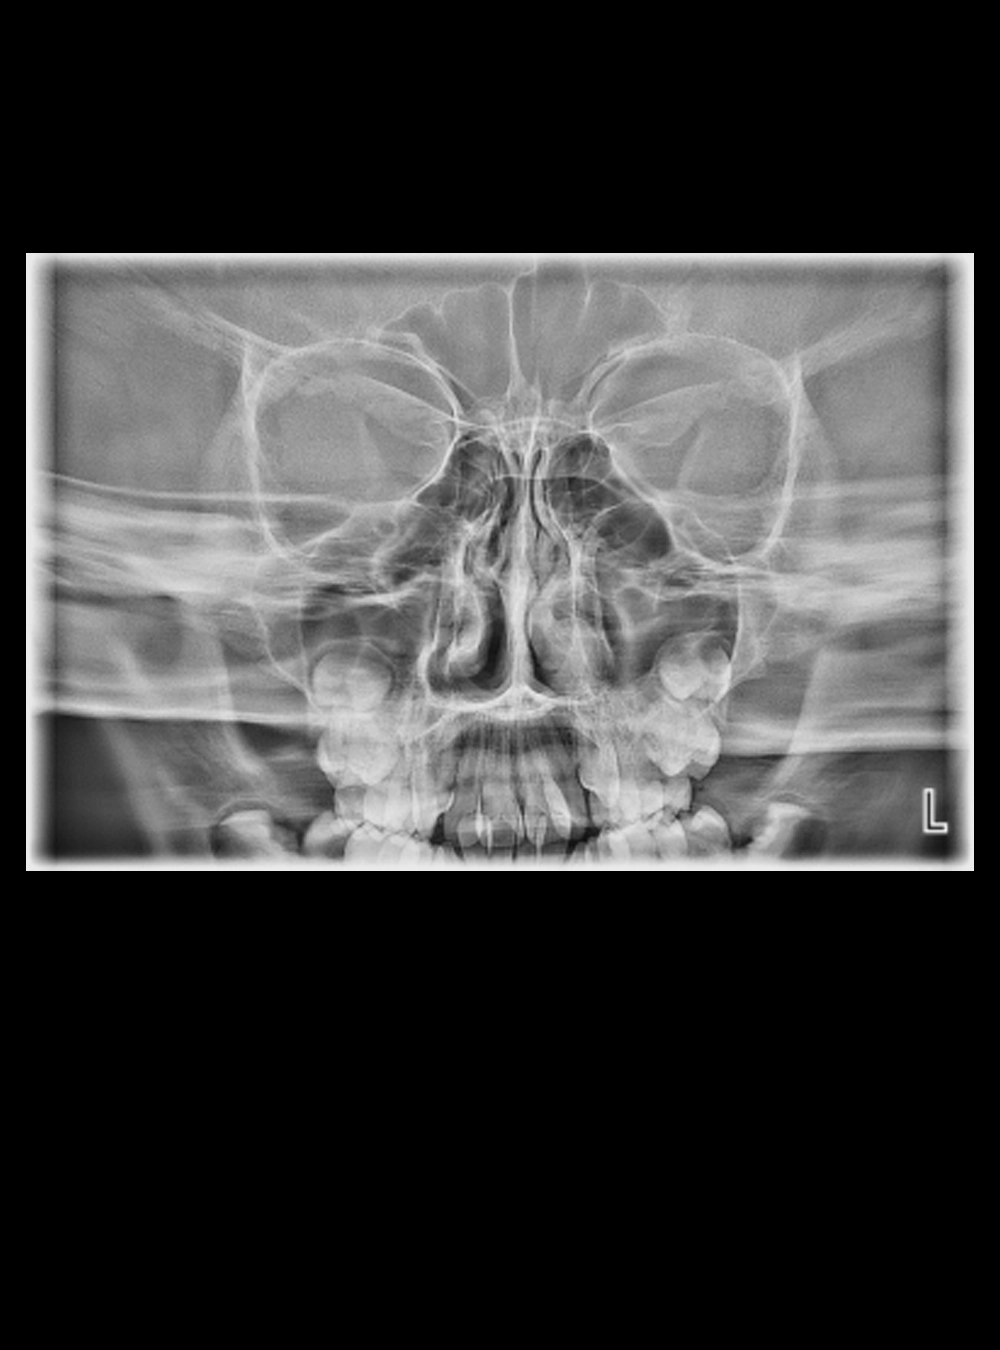

Rx P-A de Cráneo

Rx A-P de Cráneo

Rx Senos Paranasales 1 Proyección

Rx Frontal Caldwell

Rx Frontal Proyección Waters